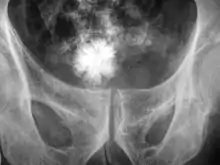

Cálculo renal

Calculose renal, conhecida vulgarmente por pedra no rim, é a presença no trato urinário de um cálculo formado a partir de sais minerais presentes na urina.[2] Os cálculos renais formam-se no rim e são geralmente expelidos do corpo na urina.[2] Os cálculos de pequena dimensão podem passar pelo trato urinário sem causar sintomas.[2] No entanto, quando um cálculo cresce mais do que 5 mm pode causar o bloqueio da uretra, provocando dor intensa na parte inferior e posterior do abdómen.[2][7] A presença de um cálculo pode também causar sangue na urina, vómitos ou dor ao urinar.[2] Cerca de metade das pessoas com episódios de calculose renal apresenta um novo episódio no prazo de dez anos.[8]